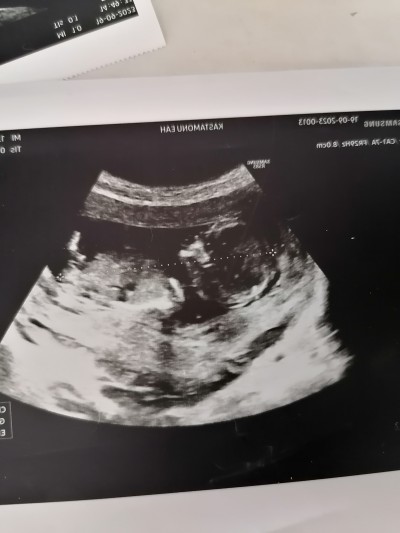

13 haftalık 3 gunluk doktora cinsiyet hakkında hiçbirsey söylemedi merak ediyorum nub teorisi dogruluk payı cok oldugunu duydum sizce ne olabilir cinsiyeti

image